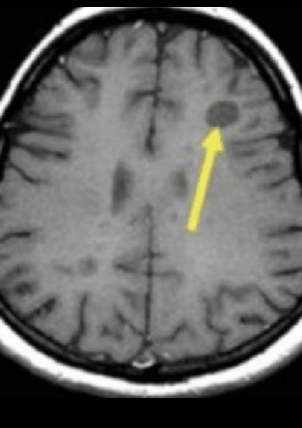

T1

Hipointensas

Black hones: crónicas

A

Black hole: crónica